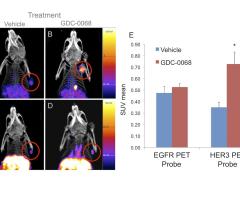

September 20, 2016 — Cancer biologists know that inhibitor-mediated feedback loop changes (increased expression of a ...